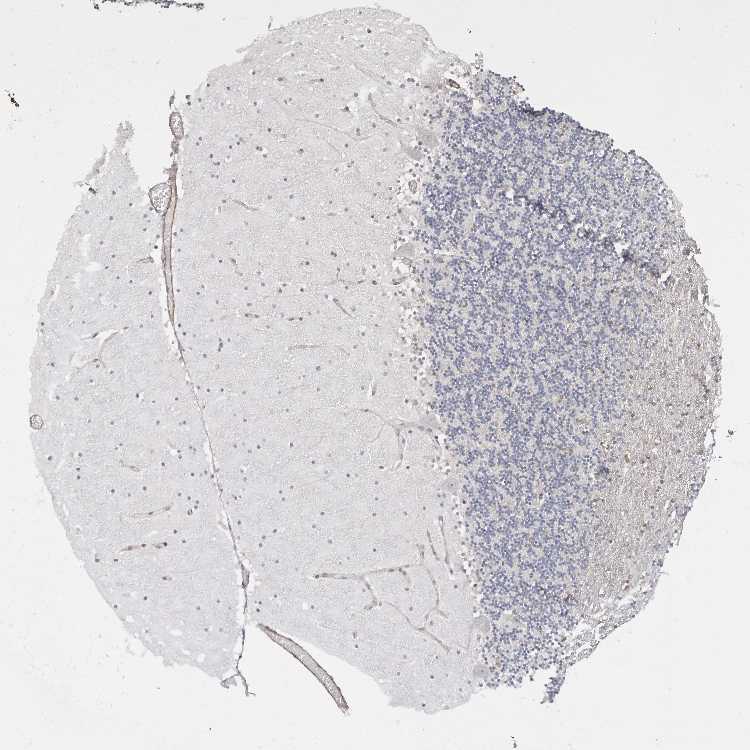

CEREBELLUM - Antibody stainingi

Antibody staining in the annotated cell types in the current human tissue is reported as not detected, low, medium, or high, based on conventional immunohistochemistry profiling in selected tissues. This score is based on the combination of the staining intensity and fraction of stained cells.

Each image is clickable and will lead to virtual microscopy that enables deeper exploration of all samples and also displays staining intensity scores, fraction scores and subcellular localization as well as patient and tissue information for each sample.

Antibody HPA027262Antibody HPA078737

Purkinje cells MediumNot detected

Cells in granular layer Not detectedMedium

Cells in molecular layer Not detectedNot detected